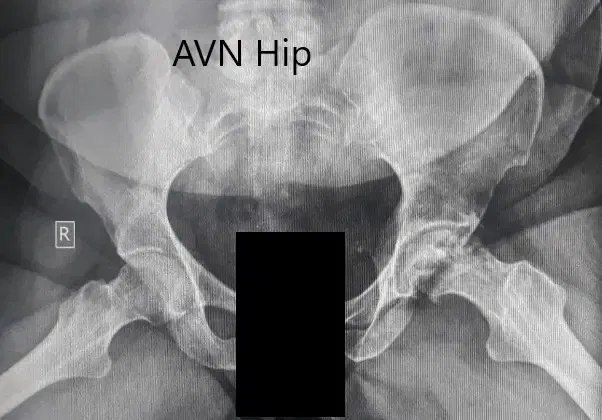

Se obtuvo una radiografía que sugería una pérdida severa de espacio articular con cambios en acetábulo en la cadera izquierda. Se perdió el contorno esférico de la cadera izquierda. Esclerosis y quistes subcondrales estaban presentes en la cadera izquierda con colapso.

Radiografía preoperatoria de la pelvis con ambas caderas en vista anteroposterior que muestra cambios en el AVN en la cadera izquierda.